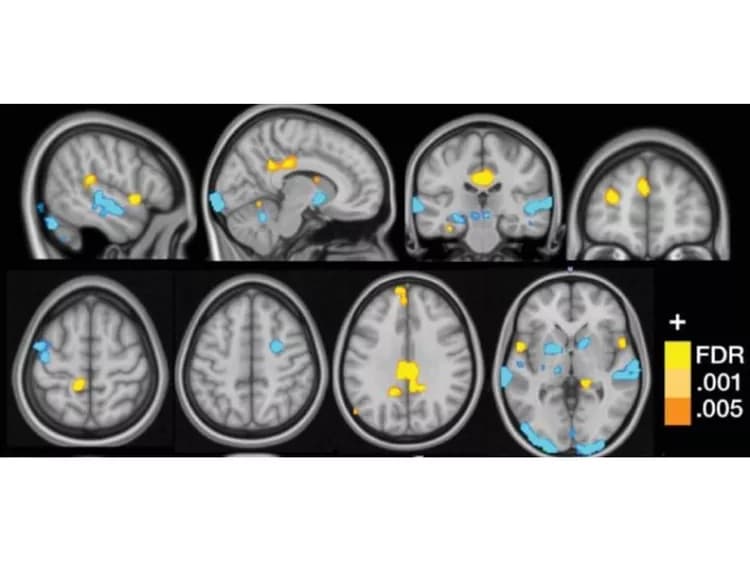

CU Boulder researchers used functional MRI scans (fMRI) to study brain activity in a group of 37 fibromyalgia patients and 35 control patients as they were exposed to a variety of non-painful visual, auditory and tactile cues as well as painful pressure.

The multisensory testing allowed the researchers to identify a series of three sub-markers, or neurological patterns, that correlated with the hypersensitivity to pain that characterizes fibromyalgia.